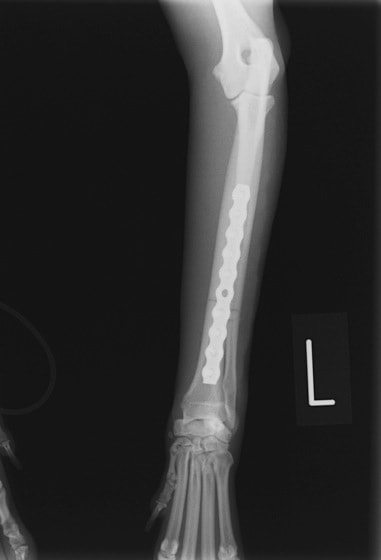

当院ではAdvanced Locking plate system(ALPS)と、Locking compression plate system(LCPS)という骨接合法で骨折症例の治療を行っています。

Advanced Locking Plate System

従来型のプレートのように広い面積で骨と接するプレートを用いて固定を行った場合、プレート下の骨はプレートとの接触面において血行が絶たれ壊死し、それがリモデリングされると骨密度が低下する。この骨密度の低下防ぐために、骨折部局所への血行を温存することの重要性が近年改めて認識されるようになってきている。Advaed Locking Plate System (ALPS)は従来型のプレートシステムの欠点を改良し、より使いやすく、より骨への血行を阻害しないようにというコンセプトで作られた。

Advanced Locking Plate System の特徴

- 骨への血行障害は最小限である

- 上下左右にベンディング可能でより3次元的な成形が可能

- すべての部位においてプレート強度は均一である

- ロッキングスクリューと圧着型スクリュー(皮質骨スクリュー)の双方が使用できる

- ダイナミックコンプレッション機能

- 生体親和性の高いチタン製

- トイ犬種から馬まで応用できるサイズ展開がある

トイプードル 右遠位橈尺骨短斜骨折のALPSによる内固定